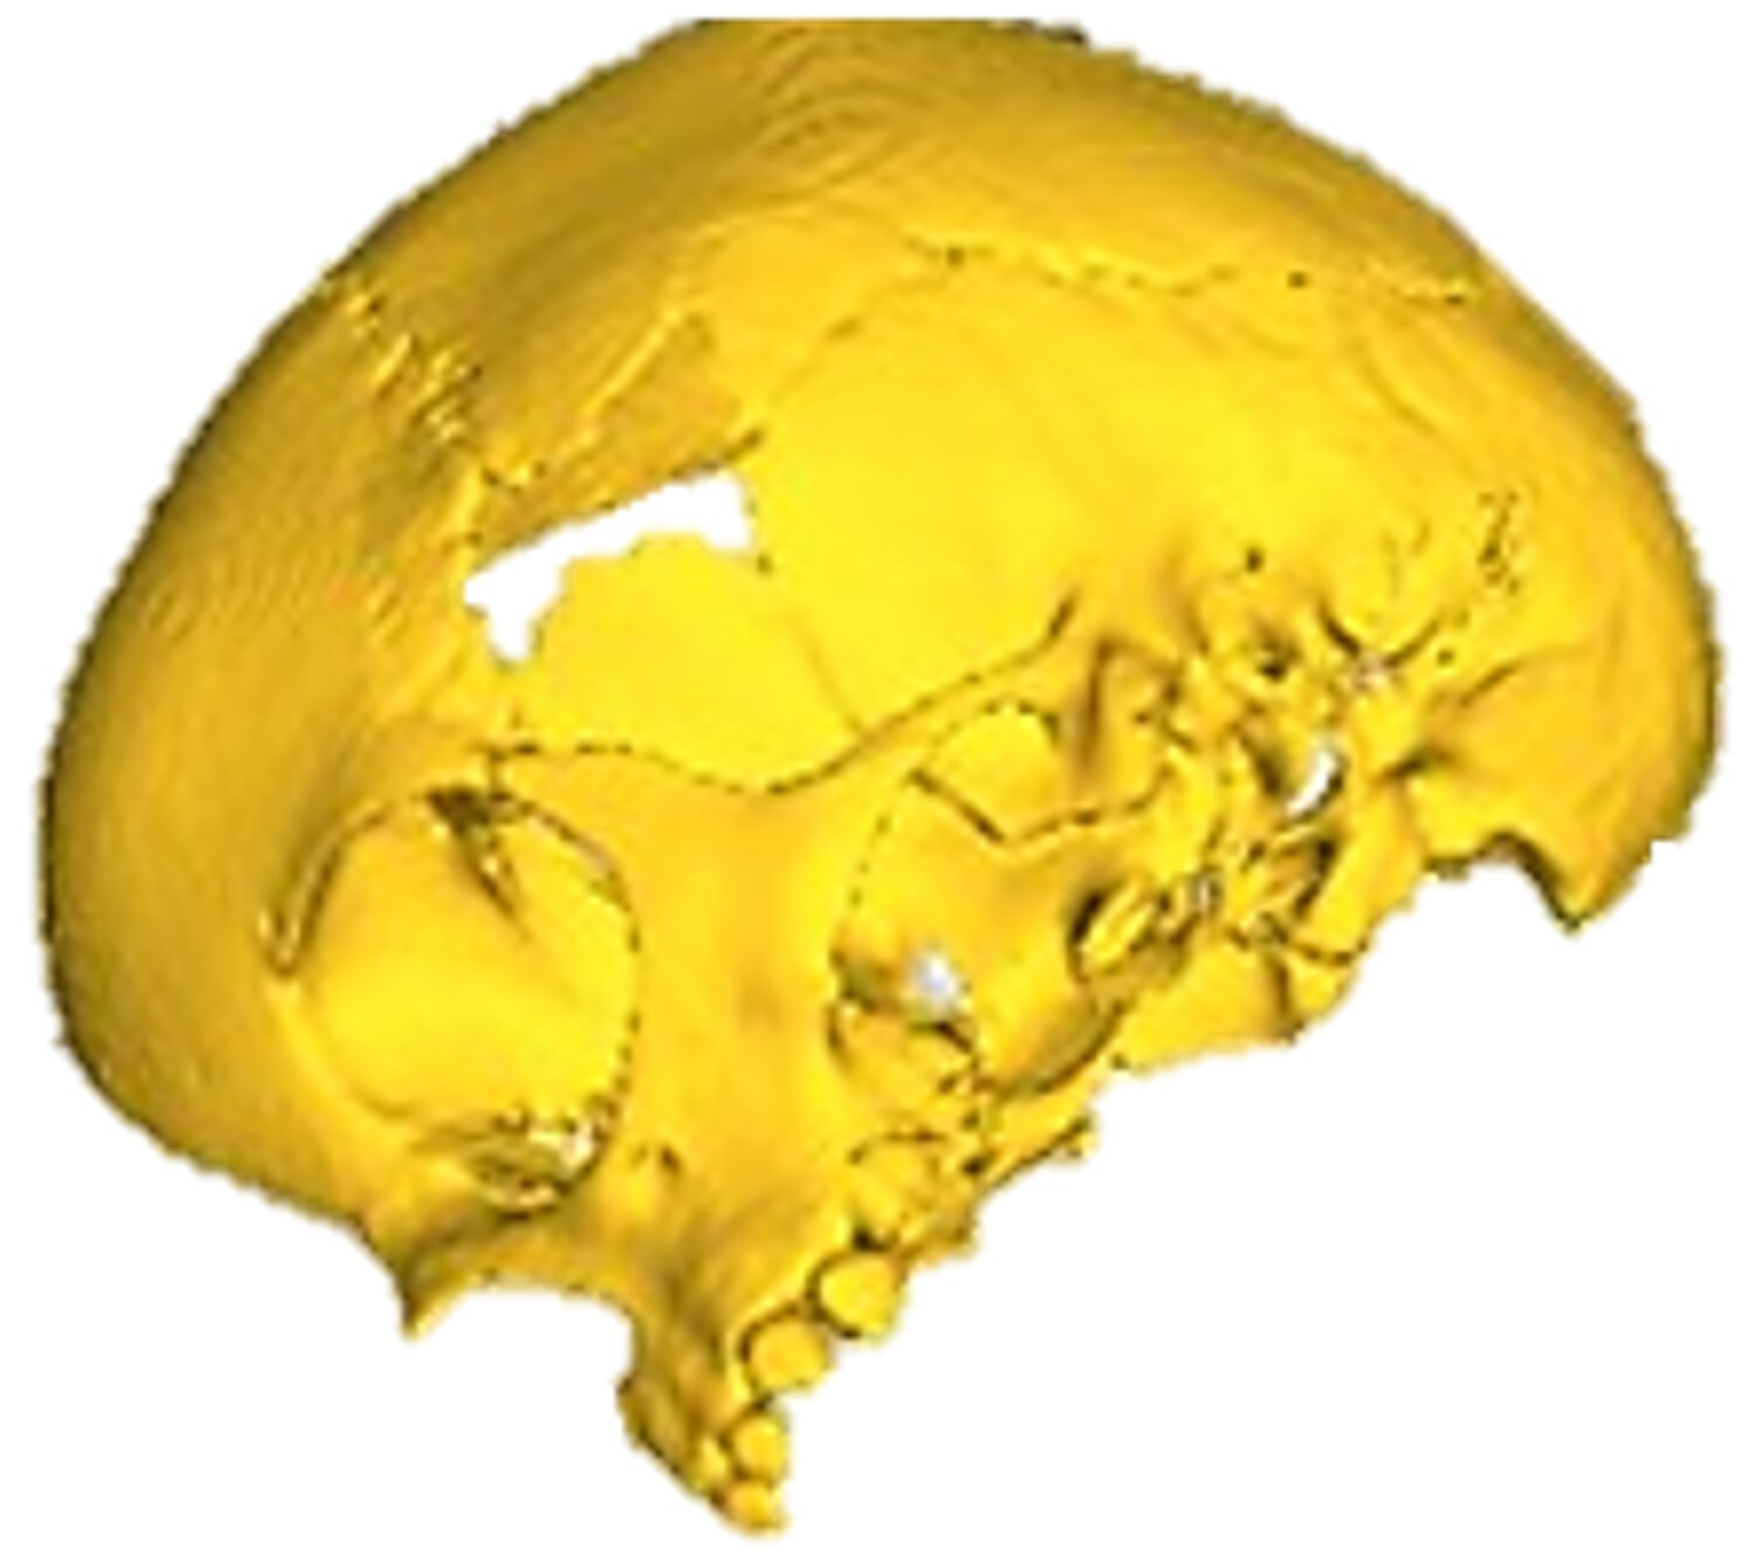

The defects identified were corroborated by both the patient’s medical history and physical examinations, as well as by tomography. The tomographic images were then segmented to reconstruct the left temporo-parietal cranial bone tissue. The density of compact cranial tissue was established using a range of 180 to 2000 HU (see Figure 3 and Figure 4).

Figure 4. Bone segmentation of the anatomical model with the cranial defect.